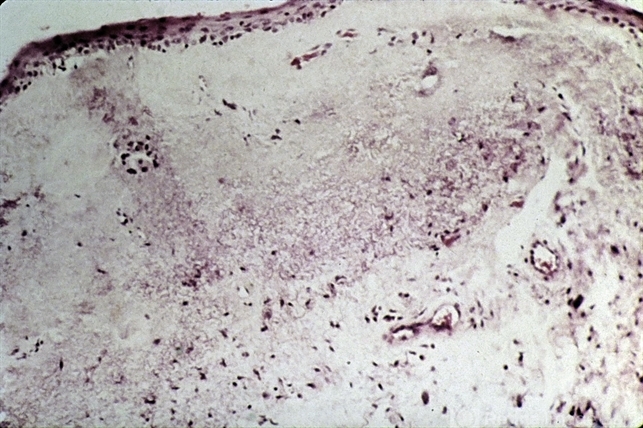

- pinguecula , actinic elastosis

- Pingueculum showing masses of fragmented fibers resembling actinic elastosis.